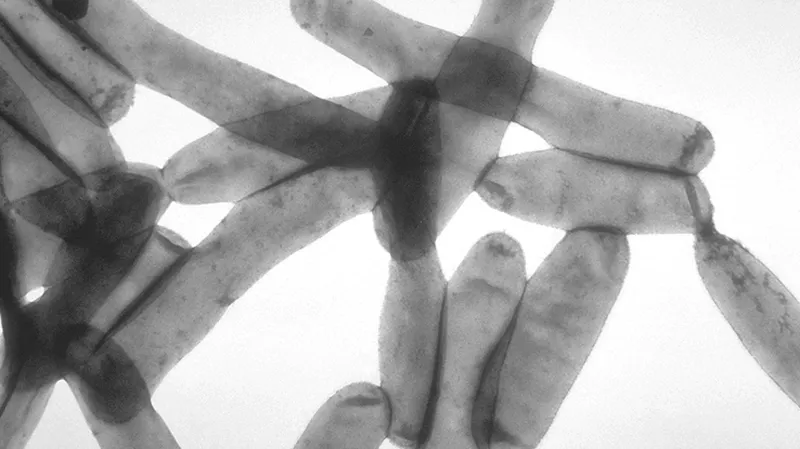

„Během své práce jsem si tu a tam v některých tkáních všiml občasné tyčinkovité bakterie, což jsem považoval za nepodstatné, protože nikdo jiný to neviděl,“ vzpomínal McDade pro americký veřejnoprávní rozhlas. Protože se nepovedlo žádnou tuto bakterii rozmnožit, považoval ji jen za kontaminaci a dál se jí nevěnoval. Mimo jiné proto, že bakterie nebyly mezi podezřelými, tím hlavním byly stále viry, zejména ty chřipkové.

Ve tkáních morčat, do nichž byla vložená plicní tkáň lidí, kteří na legionářskou nemoc zemřeli, opět nacházel osamocené tyčinkovité bakterie, ale jinak nic. V rozhovoru pro noviny tehdy přirovnal proces zkoumání této tkáně pod mikroskopem k hledání chybějící kontaktní čočky na basketbalovém hřišti s očima čtyři centimetry od podlahy.

„A najednou jsem narazil na jedno mikroskopické pole, které vypadalo, že se v něm nachází shluk mikroskopických tyčinkovitých organismů. Ne jeden, ale shluk,“ vzpomínal McDade. „Možná půl tuctu až tucet, což mi naznačovalo, že se tam na tom konkrétním místě množí.“

Když se je pokusil ze zvědavosti namnožit, zažil překvapení. Pod mikroskopem viděl těchto bakterií obrovské množství. Když pak našel s kolegy stejnou bakterii i v tkáních obětí nemoci, bylo jasné, že viník je dopaden.